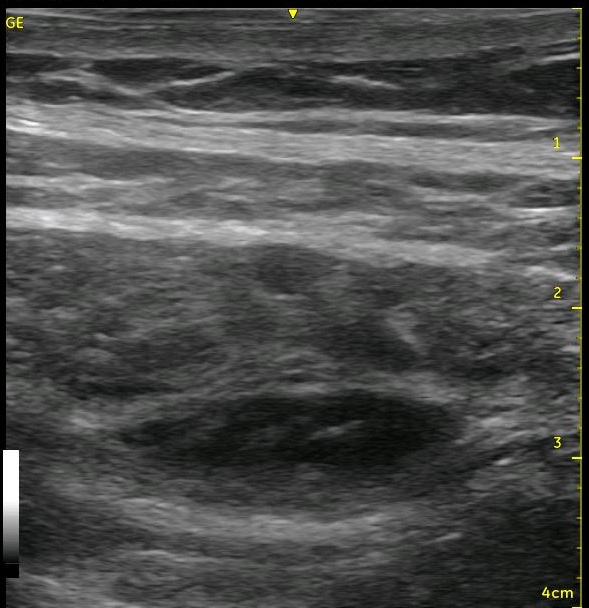

I always say that ultrasound should be used like a video, not just as a picture. The thin slice where the needle lies only gives you a very small view of what is happening within the tissues. If you are having trouble recognizing whether the spread is extending as it should, slide your probe to the ‘periphery of the spread’ where the architecture is still fully intact and visualize the spread from this location. You are starting from pristine architecture and visualizing the changes as you approach your injection site, and you will be able to see whether the local is going where you want it to go or not. Start from the pristine image and slide back toward your original position to see the changes that occur. This may be enough information for you to confirm that you are, in fact, in the correct position, and you can return to your bolusing process. [nonmember]

[ismember]Keep the images that you saw in your mind, however, so that after you begin to inject later, you will know which black areas have gotten larger if there are more than one. You have likely added local where it is supposed to go as well as in places where it is not supposed to go, and you want to know which region is expanding. This will allow you to know whether you should stay where you are injecting or withdraw or advance your needle. Either way, return to the peripheral position and visualize the changes as you continue bolusing. You will want to see a thicker and thicker black line appear between the muscle layers as you continue to inject. This is proof that your bolus is within the plane and clearly spreading above (and below since you can slide to see this same change occur on the other side of your needle) your injection site. Leaving your catheter in the space you created should allow you to maintain the size of the ‘puddle’ of local anesthetic that you have just created. You can make adjustments to your needle if you begin to see that local is clearly amassing above of below your target, and this will allow you to salvage your nerve block. This technique of ‘watching from afar’ is worth performing even in situations where the spread is obvious from the start. It will give you a better idea of the breadth of your spread, and it is a good exercise to help you to recognize and appreciate more the 3-D anatomy from the 2-D image. You can do this with other nerve blocks as well! It will help you to recognize how far to the left and right of the beam that your local spreads with your individual technique.

Look at the images below. They appear to be a series of pictures arranged from the beginning of an injection to the end. In fact, no further injection is added. The first image is taken at the periphery of a TAP block, and the subsequent images are taken as the probe is slid closer to the center of the injection. They confirm that the needle is adequately placed within the appropriate plane though the central position is a bit difficult to interpret.